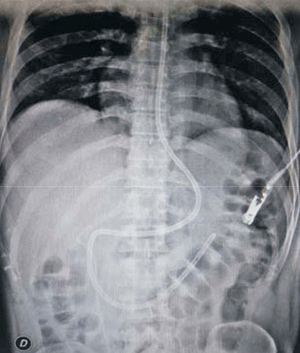

A las ocho horas posteriores al procedimiento de LEOC, instala vómitos incoercibles y dolor abdominal a predominio de hemiabdomen superior, sin fiebre. Se solicitó paraclínica de valoración general que evidenció hiperleucocitosis de 19.270 uL y amilasemia de 579 U/l; se le realizó una tomografía de abdomen que evidenció: alteraciones de la grasa peripancreática, escasa cantidad de líquido a nivel del espacio perigastroduodenal y escaso liquido libre intraabdominal; el sector cefalopancreático se observó levemente aumentado de tamaño con densidad heterogénea y se observó el catéter doble J normo posicionado a derecha. A las 48 horas, el paciente incrementó los síntomas de intolerancia digestiva, agregó distensión abdominal difusa e intensificó el dolor abdominal. En las siguientes horas instaló polipnea, taquicardia sinusal y fiebre. Se solicitó nueva paraclínica de la que se destaca una amilasemia de 1.047 U/l, proteína C reactiva (PCR) de 196 mg/l, hematocrito (HTO) de 48%, hiperleucocitosis de 21.300 µL, hiperazoemia 1,48 g/l con creatininemia de 2,24 mg/dl, funcional y enzimograma hepáticos normales. Se repitió la tomografía de abdomen que evidenció parénquima pancreático aumentado de tamaño a predominio cefálico, importante alteración de la grasa adyacente, menos de 30% de necrosis y una colección aguda peripancreática (figura 2). No se encontró evidencia de litiasis biliar ni dilatación de la vía biliar principal por ecografía ni por tomografía. El paciente se mantuvo lúcido, con elementos de síndrome de respuesta inflamatoria persistente (polipnea, taquicardia, fiebre e hiperleucitosis), presentó hipotensión arterial que fue transitoria. Durante las primeras 72 horas presentó elementos de disfunción gastrointestinal aguda grado 2, como ausencia de ruidos abdominales, vómitos persistentes y volumen residual gástrico aumentado, hipertensión intraabdominal (presión intraabdominal > o igual a 12 mmHg). El dolor se controló con opiáceos y antiinflamatorios no esteroideos; se realizó reposición de fluidos con cristaloides balanceados (suero ringer lactato) precozmente y dirigida por objetivos. Al cuarto día se inició nutrición enteral (NE) por vía yeyunal a través de una sonda naso yeyunal (SNY), con una fórmula enteral completa, polimérica, isocalórica, isonitrogenada y sin fibras (figura 3). El paciente no presentó elementos de intolerancia a la NE.